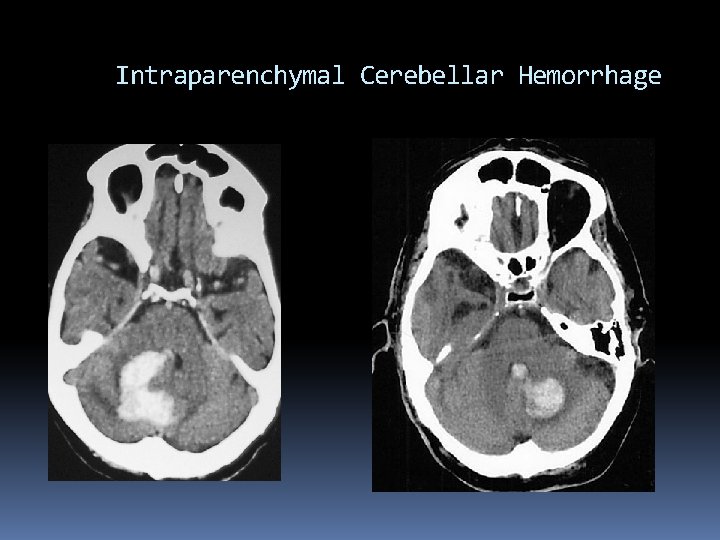

Intracranial Hemorrhage Cerebellar Hemorrhage Sudden onset of vertigo, severe N/V, and ataxia leading to altered mental status and coma over a few hours Obstructive hydrocephalus can contribute to brainstem herniation Urgent posterior fossa decompression is essential for survival

Intraparenchymal Cerebellar Hemorrhage